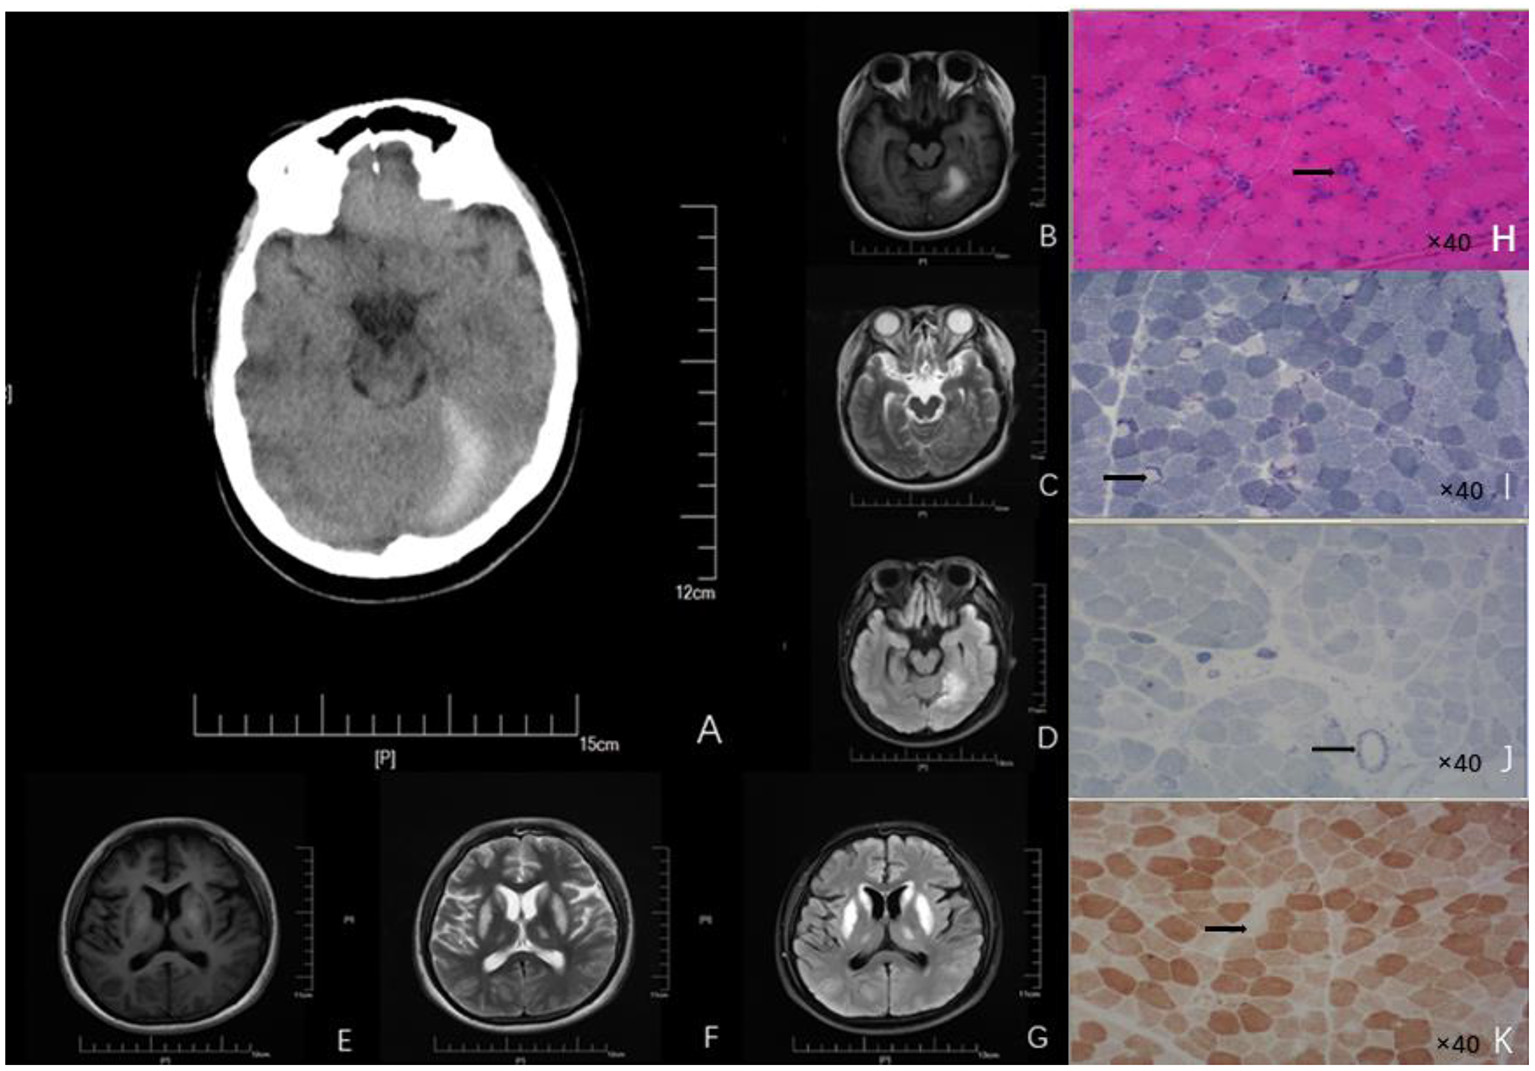

Figure 1

Neuroimages (A–G) and skeletal muscle biopsy (H–K) of this patient. (A) Craniocerebral CT showed high-density signal on the left side of the tentorial cerebellum, indicating subdural hematoma. Patchy abnormal signals are seen on the left tentorium of the cerebellum. (B) High intensity in T1 scan. (C) Slightly high intensity on T2 scan. (D) Significantly - high intensity on FLAIR scan). Symmetrical patchy abnormal signals could be found in bilateral lentiform nucleus, caudate nucleus head, and ventrolateral nucleus. (E) Low signal intensity in T1 scans. (F) Slight-higher signal intensity in T2 scans. (G) Obvious-high signal intensity in FLAIR scans. (H) HE findings of the skeletal muscle biopsy (right biceps muscle) revealed that the diameter of muscle fibers varied greatly; Atrophic muscle fibers were scattered in round and small circles together with large number of necrotic and regenerated muscle fibers (black arrow; 40× magnification). (I) NADH staining revealed uneven enzyme activity in some muscle fibers and dense staining around the muscle fibers (black arrow, 40× magnification). (J) SDH staining revealed SSV and several black arrow (black arrow; 40× magnification). (K) COX staining revealed negative-stained muscle fibers (black arrow; 40× magnification). HE, Hematoxylin-eosin; NADH, Nicotinamide adenine dinucleotide; CT, Computed tomography; FLAIR, Fluid attenuated inversion recovery.

We suggest that relying only on the abnormal changes evident on MRI and CT is not sufficient to distinguish PA from other metabolic diseases, especially Leigh syndrome. Therefore, muscle pathological examination should be performed to detect the presence of other metabolic diseases. In muscle pathology, Leigh syndrome usually shows different sizes of muscle fibers, in which lipid deposition is common, atrophic muscle fibers are mostly type II, atypical RRFs can be seen, and loss of COX enzyme activity is evident in some patients' muscle fibers and blood vessel walls (11). In contrast, the muscle pathology in mitochondrial encephalomyopathy with lactic acidosis and stroke-like seizure syndrome (MELAS) tends to show a scattered distribution of RRFs and strong SSVs (12). In our case, great variation in the muscle fiber diameter was observed, and a large number of necrotic and regenerated muscle fibers were evident. RRF was not found in GT staining. NADH staining showed that some of the enzyme activities were uneven. SSV was evident on SDH staining. Several COX-negative muscle fibers were made visible by COX staining. Several necrotic muscle fibers were positive for acid staining. Staining for NADH, COX, and SDH showed that the enzyme activity in some muscle fibers was uneven, indicating that the mitochondrial inner membrane respiratory chain function was abnormal. Combined with previous studies, this suggested that a decrease in PCC activity caused an accumulation of propionyl CoA in the mitochondria (13). This would inhibit the electron transfer function of complex IV cytochrome C oxidase in the mitochondrial inner membrane and interrupt the electron transfer process of the mitochondrial respiratory chain (14). Abnormal oxidative phosphorylation involves skeletal muscle, making the pathological characteristics of muscle in PA similar to that of metabolic myopathy. This suggests that PA involving skeletal muscle should be classified into the category of metabolic myopathy. The pathological features of delayed-onset PA in muscles are reported rarely in the literature. Therefore, our case provides valuable information about the pathological features of muscles in PA.